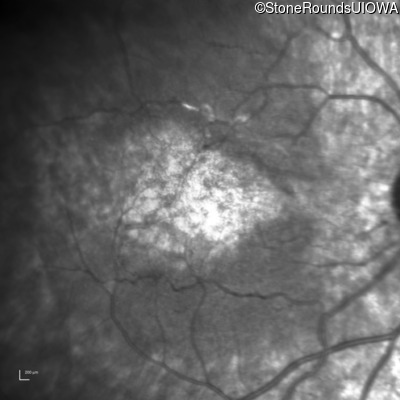

Infrared Fundus Photograph - Right - 20/160

Exemplar